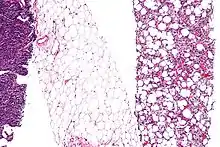

Fig. 2 Micrograph of a dedifferentiated liposarcoma tumor.jpg.webp) Fig. 3 Lower-power micrograph of myxoid liposarcoma tumor

Fig. 3 Lower-power micrograph of myxoid liposarcoma tumor.JPG.webp) Fig. 4 Higher-power micrograph of myxoid liposarcoma tumor

Histopathologic analyses of MLS (see Figs. 3 and 4 in the below Histopathology of liposarcomas section) reveals cells scattered throughout a myxoid matrix (i.e. a connective tissue background that appears more blue or purple than the red color of normal connective tissue when these tissues are properly prepared, H&E stained, and viewed microscopically). These cells are lipoblasts, some of which are signet ring-shaped (a shape suggesting that the cell may be neoplastic), oval-shaped, or round-shaped.[40] MLS tumors may be hypercellular and contain solid sheets of round cells that comprise at least 5% of all cells or low cellularity populated with cells that have bland nuclei and <5% round cells in a background of curving capillaries resembling a chicken-wire pattern. Tumors that contain at least 5% round cells are classified as high-grade while those with <5% round cells are classified as low-grade.[39] High-grade MLS tumors typically take a more aggressive clinical course than low-grade MLS tumors.[40]